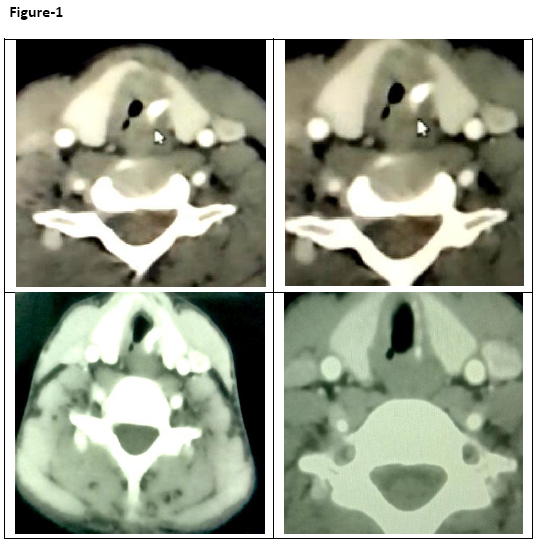

Contrast Enhanced Computed Tomography (CECT) examination of the neck was performed which revealed moderate focal subglottic tracheal stenosis 2.0 cm below the vocal cords with a transverse luminal diameter of less than 2.0 mm (Figure-1). The antero-posterior luminal diameter was 9 mm at the level of stenosis. Flexible fibreoptic bronchoscopy revealed normal vocal cords and subglottic tracheal stenosis with luminal opening of 1.5-1.8 mm with a thickened trachea around the small opening. Even, scope of 2.2 mm diameter could not be negotiated through small tracheal opening (Figure-2). Endotracheal biopsy was taken from around the thickened tracheal luminal opening which revealed fragments of stratified squamous epithelium revealing acanthosis, exocytosis and neutrophils showing mild to moderate reactive atypia.

Figure-1: CECT of neck showing moderate focal subglottic stenosis 2.0 cm below the vocal cords